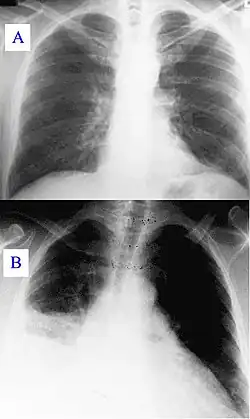

Radiografia de tórax

Na medicina, uma radiografia de tórax, comumente chamada de raio-x de tórax, é uma radiografia do tórax usada para diagnosticar doenças que afetem o tórax, seu conteúdo e suas estruturas próximas. As radiografias de tórax estão entre os filmes diagnósticos mais realizados, sendo úteis no diagnóstico de muitas doenças.

Com a radiografia de tórax avalia-se os pulmões, tamanho e contornos do coração, mediastino, pleura, diafragma e os ossos da caixa torácica (costelas, esterno e vértebras).